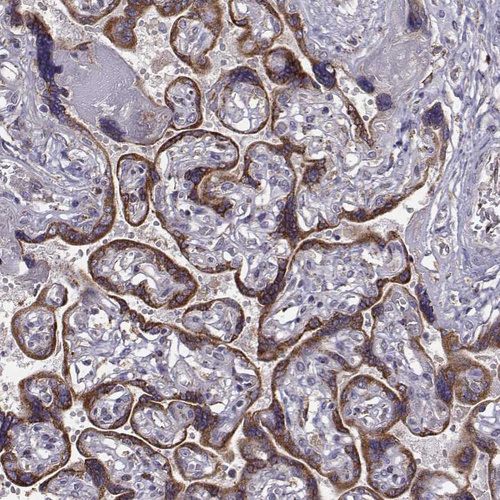

Immunohistochemistry analysis in human cerebral cortex and skeletal muscle tissues using HPA064125 antibody. Corresponding SELENOI RNA-seq data are presented for the same tissues.